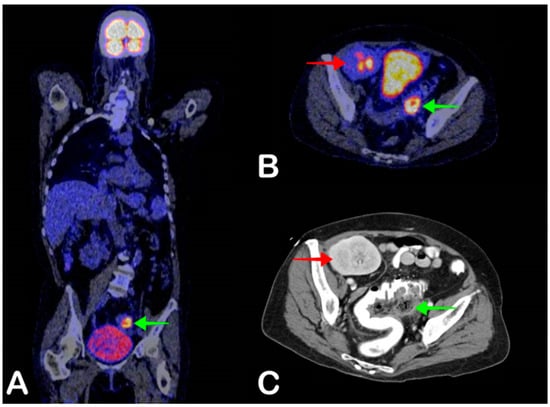

3. Limitations of FDG-PET/CT

- Torres, V.E.; Harris, P.C.; Pirson, Y. Autosomal dominant polycystic kidney disease. Lancet 2007, 369, 1287–1301. [Google Scholar] [CrossRef]

- Oh, J.; Shin, C.-I.; Kim, S.Y. Infected cyst in patients with autosomal dominant polycystic kidney disease: Analysis of computed tomographic and ultrasonographic imaging features. PLoS ONE 2018, 13, e0207880. [Google Scholar] [CrossRef]

- Lantinga, M.A.; Drenth, J.P.; Gevers, T.J.G. Diagnostic criteria in renal and hepatic cyst infection. Nephrol. Dial. Transpl. 2014, 30, 744–751. [Google Scholar] [CrossRef]

- Lantinga, M.A.; Casteleijn, N.F.; Geudens, A.; De Sévaux, R.G.; Van Assen, S.; Leliveld, A.M.; Gansevoort, R.T.; Drenth, J.P. Management of renal cyst infection in patients with autosomal dominant polycystic kidney disease: A systematic review. Nephrol. Dial. Transpl. 2016, 32, 144–150. [Google Scholar] [CrossRef] [PubMed]

- Sallée, M.; Rafat, C.; Zahar, J.-R.; Paulmier, B.; Grünfeld, J.-P.; Knebelmann, B.; Fakhouri, F. Cyst Infections in Patients with Autosomal Dominant Polycystic Kidney Disease. Clin. J. Am. Soc. Nephrol. 2009, 4, 1183–1189. [Google Scholar] [CrossRef] [PubMed]

- Bobot, M.; Ghez, C.; Gondouin, B.; Sallée, M.; Fournier, P.; Burtey, S.; Legris, T.; Dussol, B.; Berland, Y.; Souteyrand, P.; et al. Diagnostic performance of [18F] fluorodeoxyglucose positron emission tomography–computed tomography in cyst infection in patients with autosomal dominant polycystic kidney disease. Clin. Microbiol. Infect. 2016, 22, 71–77. [Google Scholar] [CrossRef] [PubMed]

- Jouret, F.; Lhommel, R.; Beguin, C.; Devuyst, O.; Pirson, Y.; Hassoun, Z.; Kanaan, N. Positron-Emission Computed Tomography in Cyst Infection Diagnosis in Patients with Autosomal Dominant Polycystic Kidney Disease. Clin. J. Am. Soc. Nephrol. 2011, 6, 1644–1650. [Google Scholar] [CrossRef] [PubMed]

- Pijl, J.P.; Glaudemans, A.W.; Slart, R.H.; Kwee, T.C. 18F-FDG PET/CT in Autosomal Dominant Polycystic Kidney Disease Patients with Suspected Cyst Infection. J. Nucl. Med. 2018, 59, 1734–1741. [Google Scholar] [CrossRef]